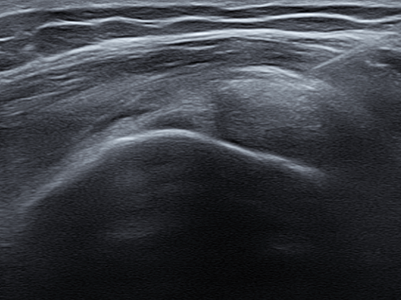

Calcific Tendinitis

어깨에 석회가 쌓이는 석회성 건염

석회성 건염이란 어깨를 둘러싸고 있는 힘줄인 회전근개에

칼슘 성분의 석회 물질이 쌓이면서 염증과 통증을 유발하는 질환입니다.

남성보다 여성에게 더 자주 나타나며,

어깨를 많이 사용하는 직업군에서도 잘 발생합니다.

석회성 건염은 어깨 힘줄에 석회질이 침착되면서

염증과 극심한 통증을 유발하는 질환입니다.

하지만 대부분의 경우 수술 없이도, 정확한 진단과

적절한 비수술 치료만으로 증상의 호전을 기대할 수 있습니다.